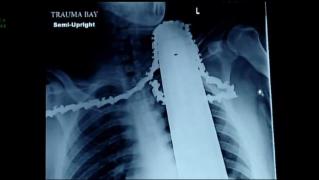

Lama fierăstrăului i-a străpuns gâtul, dar a scăpat uluitor!

Lama fierăstrăului i-a străpuns gâtul, dar a scăpat uluitor!Un bărbat care trebuia să cosmetizeze câţiva copaci a fost la un pas de tragedie

pe 02.04.2014 la 13:24